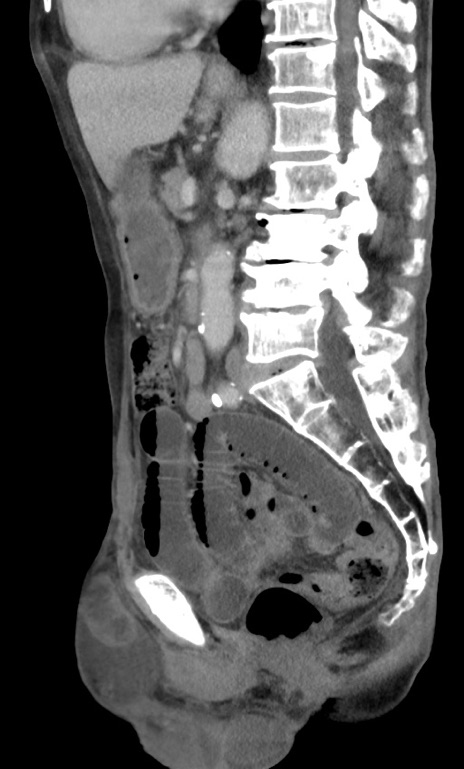

冠状断像

【症例】 70歳代男性

【主訴】右鼠径部腫瘤、疼痛

【現病歴】本日朝より上記主訴あり、受診。

【既往歴】膀胱癌にて膀胱全摘、両側尿管皮膚瘻

【データ】WBC 5600、CRP 0.56